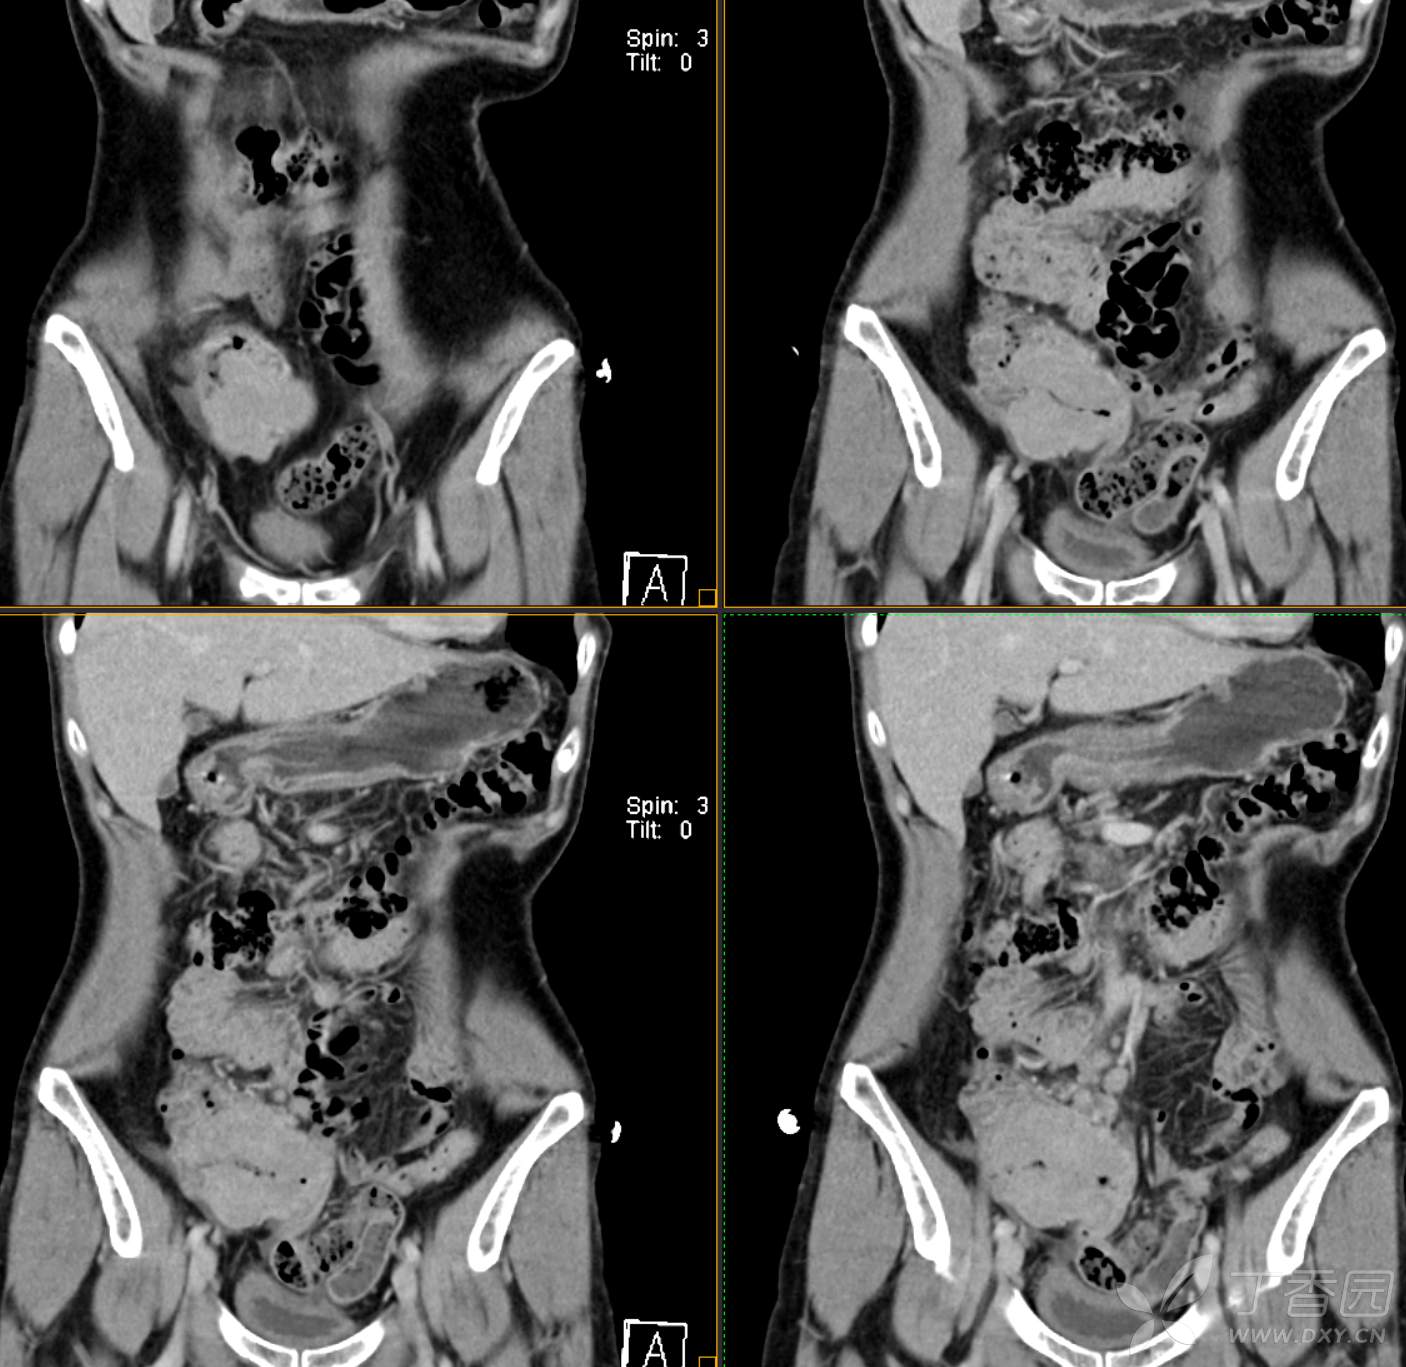

腹组13:患者,女,62岁,大便习惯改变2月余

主 诉: 【大便性状改变2月余】

现病史: 患者2月余前无明显诱因下出现大便次数增多,无明显血便黑便及粘液脓血便,大便次数由1次/日增加至2-3次/日,大便形状变细如小指,偶稀软不成形,无腹痛腹胀腹泻,无恶心呕吐、胸闷气促,肛门排气通畅,无发热盗汗。至当地医院就诊,行肠镜检查发现"回盲部占位"。为进一步治疗,我院门诊拟"回盲部肿瘤"收住入院。